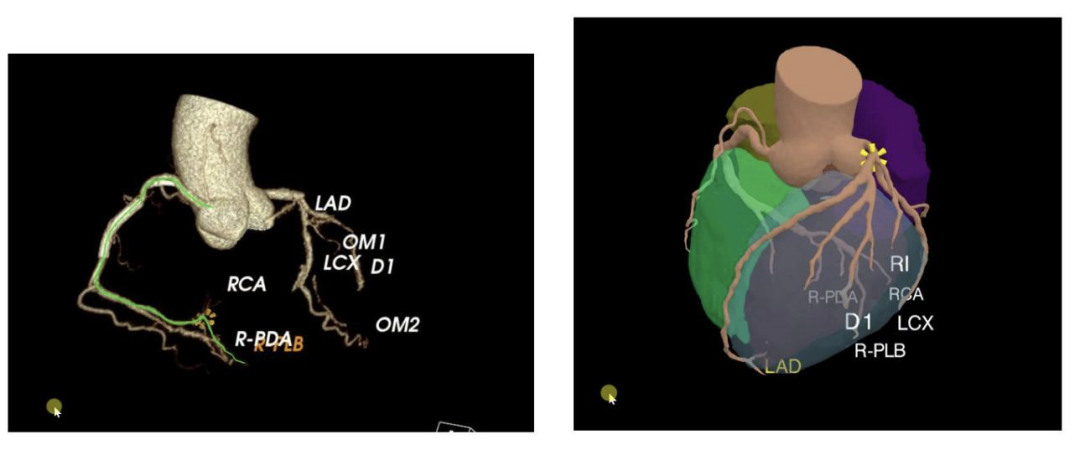

冠心病的诊断是一个什么样的过程?首先需要做一个冠脉 CTA,得到一个比较清晰的血管影像,医生第一步需要在三维图像里分割出血管,血管用红色区域来表示,分割过程是医生在一个传统工作站上通过半手工加半自动图像处理算法完成的,一根一根血管去分割就可以重构出整个心血管的树状结构。基于这个树状结构医生可以根据专业经验判断出要查看哪一根血管,看其中有无病灶或者钙化,导致血管堵塞或血管狭窄。

如图是一个重建出来的三维血管图示,左边是血管的渲染效果,右边增加了心肌之后整个心脏的重建效果。

基于这样的三维重建,我们可以把 CPR 图,短轴图、拉直图三种不同的可视化方法以一个统一的界面展现在产品中,方便医生以更高的效率选择观察什么样的血管,观察什么位置以及分割的结果,结合医生自己的经验对病灶的情况做出判断。这种方式既有算法自动输出的结果,同时也允许医生基于自己的理解对于算法的结果做一些修改,这是一个 AI 和医生协同工作的过程。